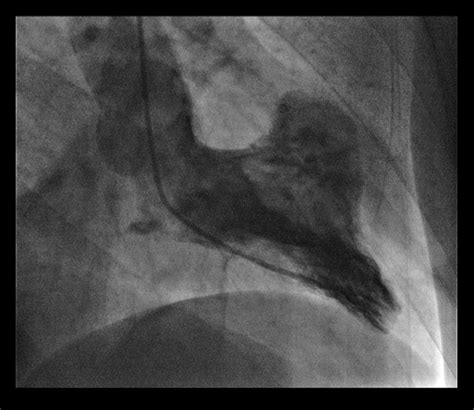

• Cardiac Catheterization: This invasive procedure involves inserting a catheter into the heart to measure pressure and blood flow, and to visualize the coronary arteries.